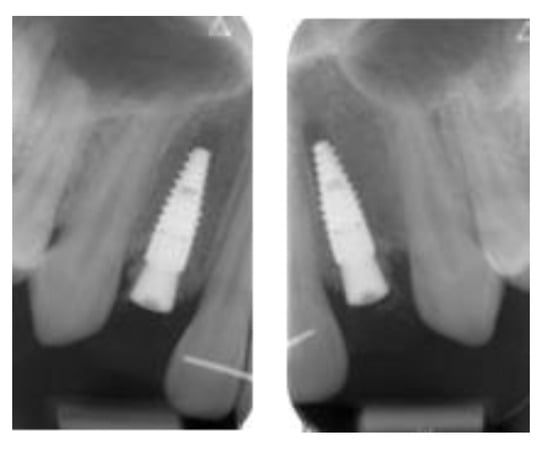

2.4.1. Radiographic Measurements

3.2. Marginal Bone Level Outcomes

| Mesial Marginal Bone Level (2D) [mm] after Immediate Placement | ||||||||

|---|---|---|---|---|---|---|---|---|

| Patient | 1 | 2 | 3 | 4 | 5 | Median | IQR | |

| Implant position | 45 | 35 | 45 | 45 | 13 | 23 | NA | NA |

| Post-OP mesial | 1.8 | 0.0 | 0.1 | 3.0 | 0.4 | 0.4 | 0.4 | 0.18–1.45 |

| 1 year mesial | 0.6 | 0.0 | 0.1 | 1.5 | 0.1 | 0.1 | 0.1 | 0.1–0.48 |

| Post-OP distal | 1.2 | 0.0 | 0.1 | 3.0 | 0.4 | 0.4 | 0.4 | 0.18–1.0 |

| 1 year distal | 0.6 | 0.0 | 0.1 | 1.5 | 0.2 | 0.0 | 0.2 | 0.03–0.5 |

| Marginal Bone Level (2D) [mm] after Delayed Placement | ||||||||

| Implant position | 35 | 45 | 35 | 35 | 35 | 45 | NA | NA |

| Post-OP mesial | 2.0 | 1.0 | 0.2 | 0.6 | 0.2 | 0.2 | 0.4 | 0.2–0.9 |

| 1 year mesial | 1.6 | 0.5 | 0.0 | 0.3 | 0.1 | 0.1 | 0.3 | 0.1–0.45 |

| Post-OP distal | 0.0 | 0.5 | 0.0 | 0.6 | 0.1 | 0.1 | 0.1 | 0.03–0.4 |

| 1 year distal | 0.0 | 0.2 | 0.0 | 0.3 | 0.1 | 0.1 | 0.1 | 0.03–0.18 |